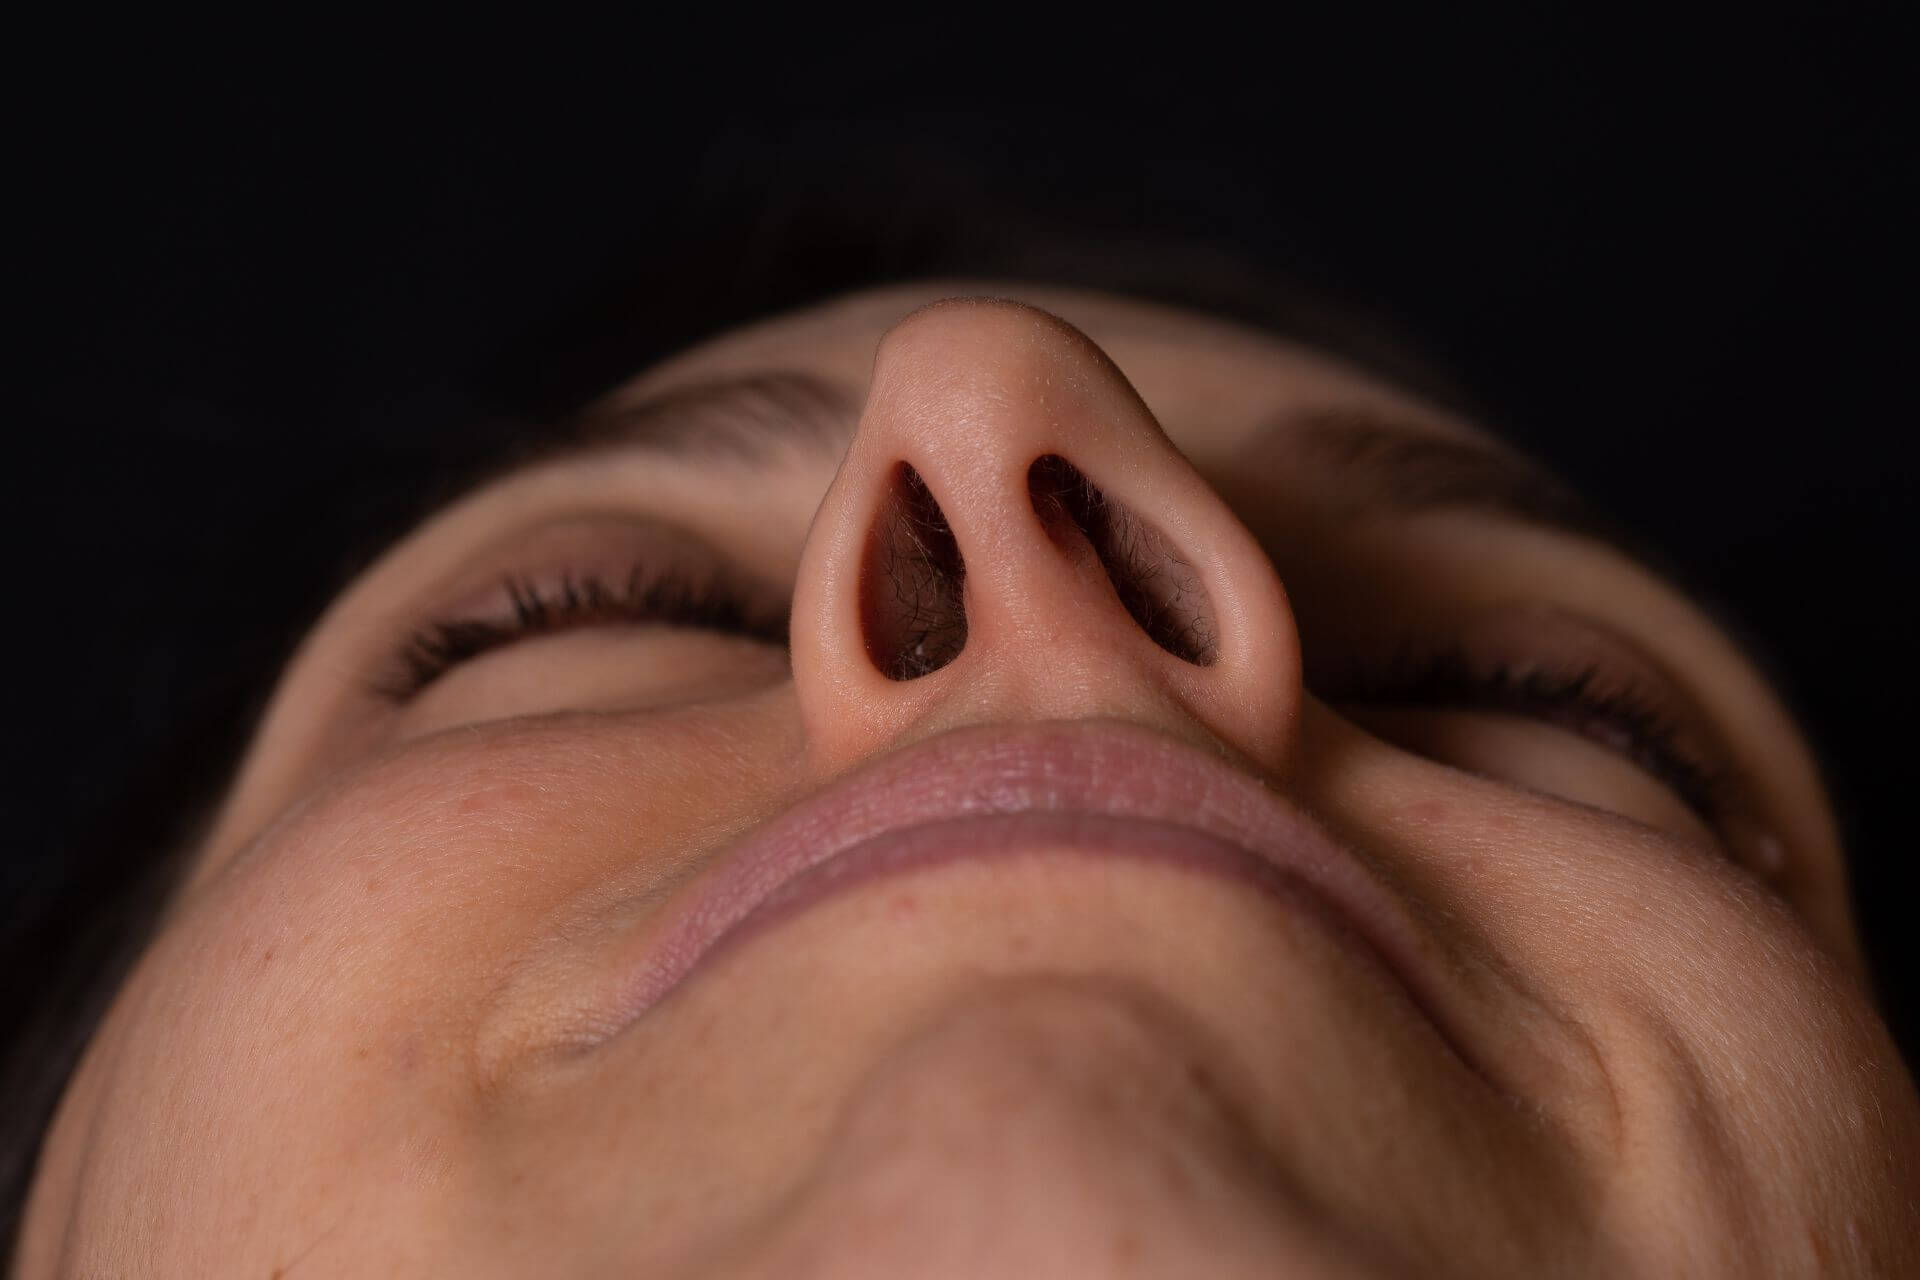

The nasal septum is the middle divider that separates your right and left nasal cavities. When the septum is not straight, or is deviated, it may obstruct one side of your nasal breathing more than the other.

A deviated septum may cause other problems such as recurrent nosebleeds, congestion due to refractory turbinate engorgement, recurrent sinus infections, nasal or sinus pain, and external changes to the nose.

Septoplasty involves the surgical correction to straighten a deviated septum.

Septoplasty involves the surgical correction to straighten a deviated septum. This is typically done through incisions placed inside the nose. The lining of the septum is raised in order to access the underlying cartilage and bone. The damaged portions contributing to deviation are removed. The goal is to straighten the septum and provide equal breathing on the right and left sides.